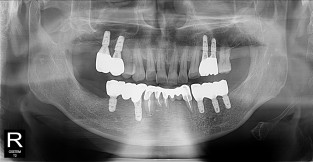

• 10

풀케이스

치료기간 : 2022-03-18 ~ 2023-09-15

1. 상기 x-ray 이미지 모두 동일한 해당 의료기관에서 진료한 환자입니다.

2. 상기 x-ray 이미지 모두 동일 인물의 것입니다.

3. 치료 전 이미지는 2022-03-18에 촬영했으며, 치료 후 이미지는 2023-09-15에 촬영하였습니다.

4. 상기 x-ray 이미지 모두 동일 조건에서 환자분의 동의를 받아촬영되었습니다.

* 임플란트 시술은 환자분의 상태(고혈압, 당뇨 등)에 따라 부작용이 있을 수 있으니, 반드시 전문의와 상담이 필요합니다.

* 임플란트 수술 부작용

: 수술 후 출혈, 교합, 통증, 붓기, 염증 등의 문제점이 발생할 수 있습니다.)